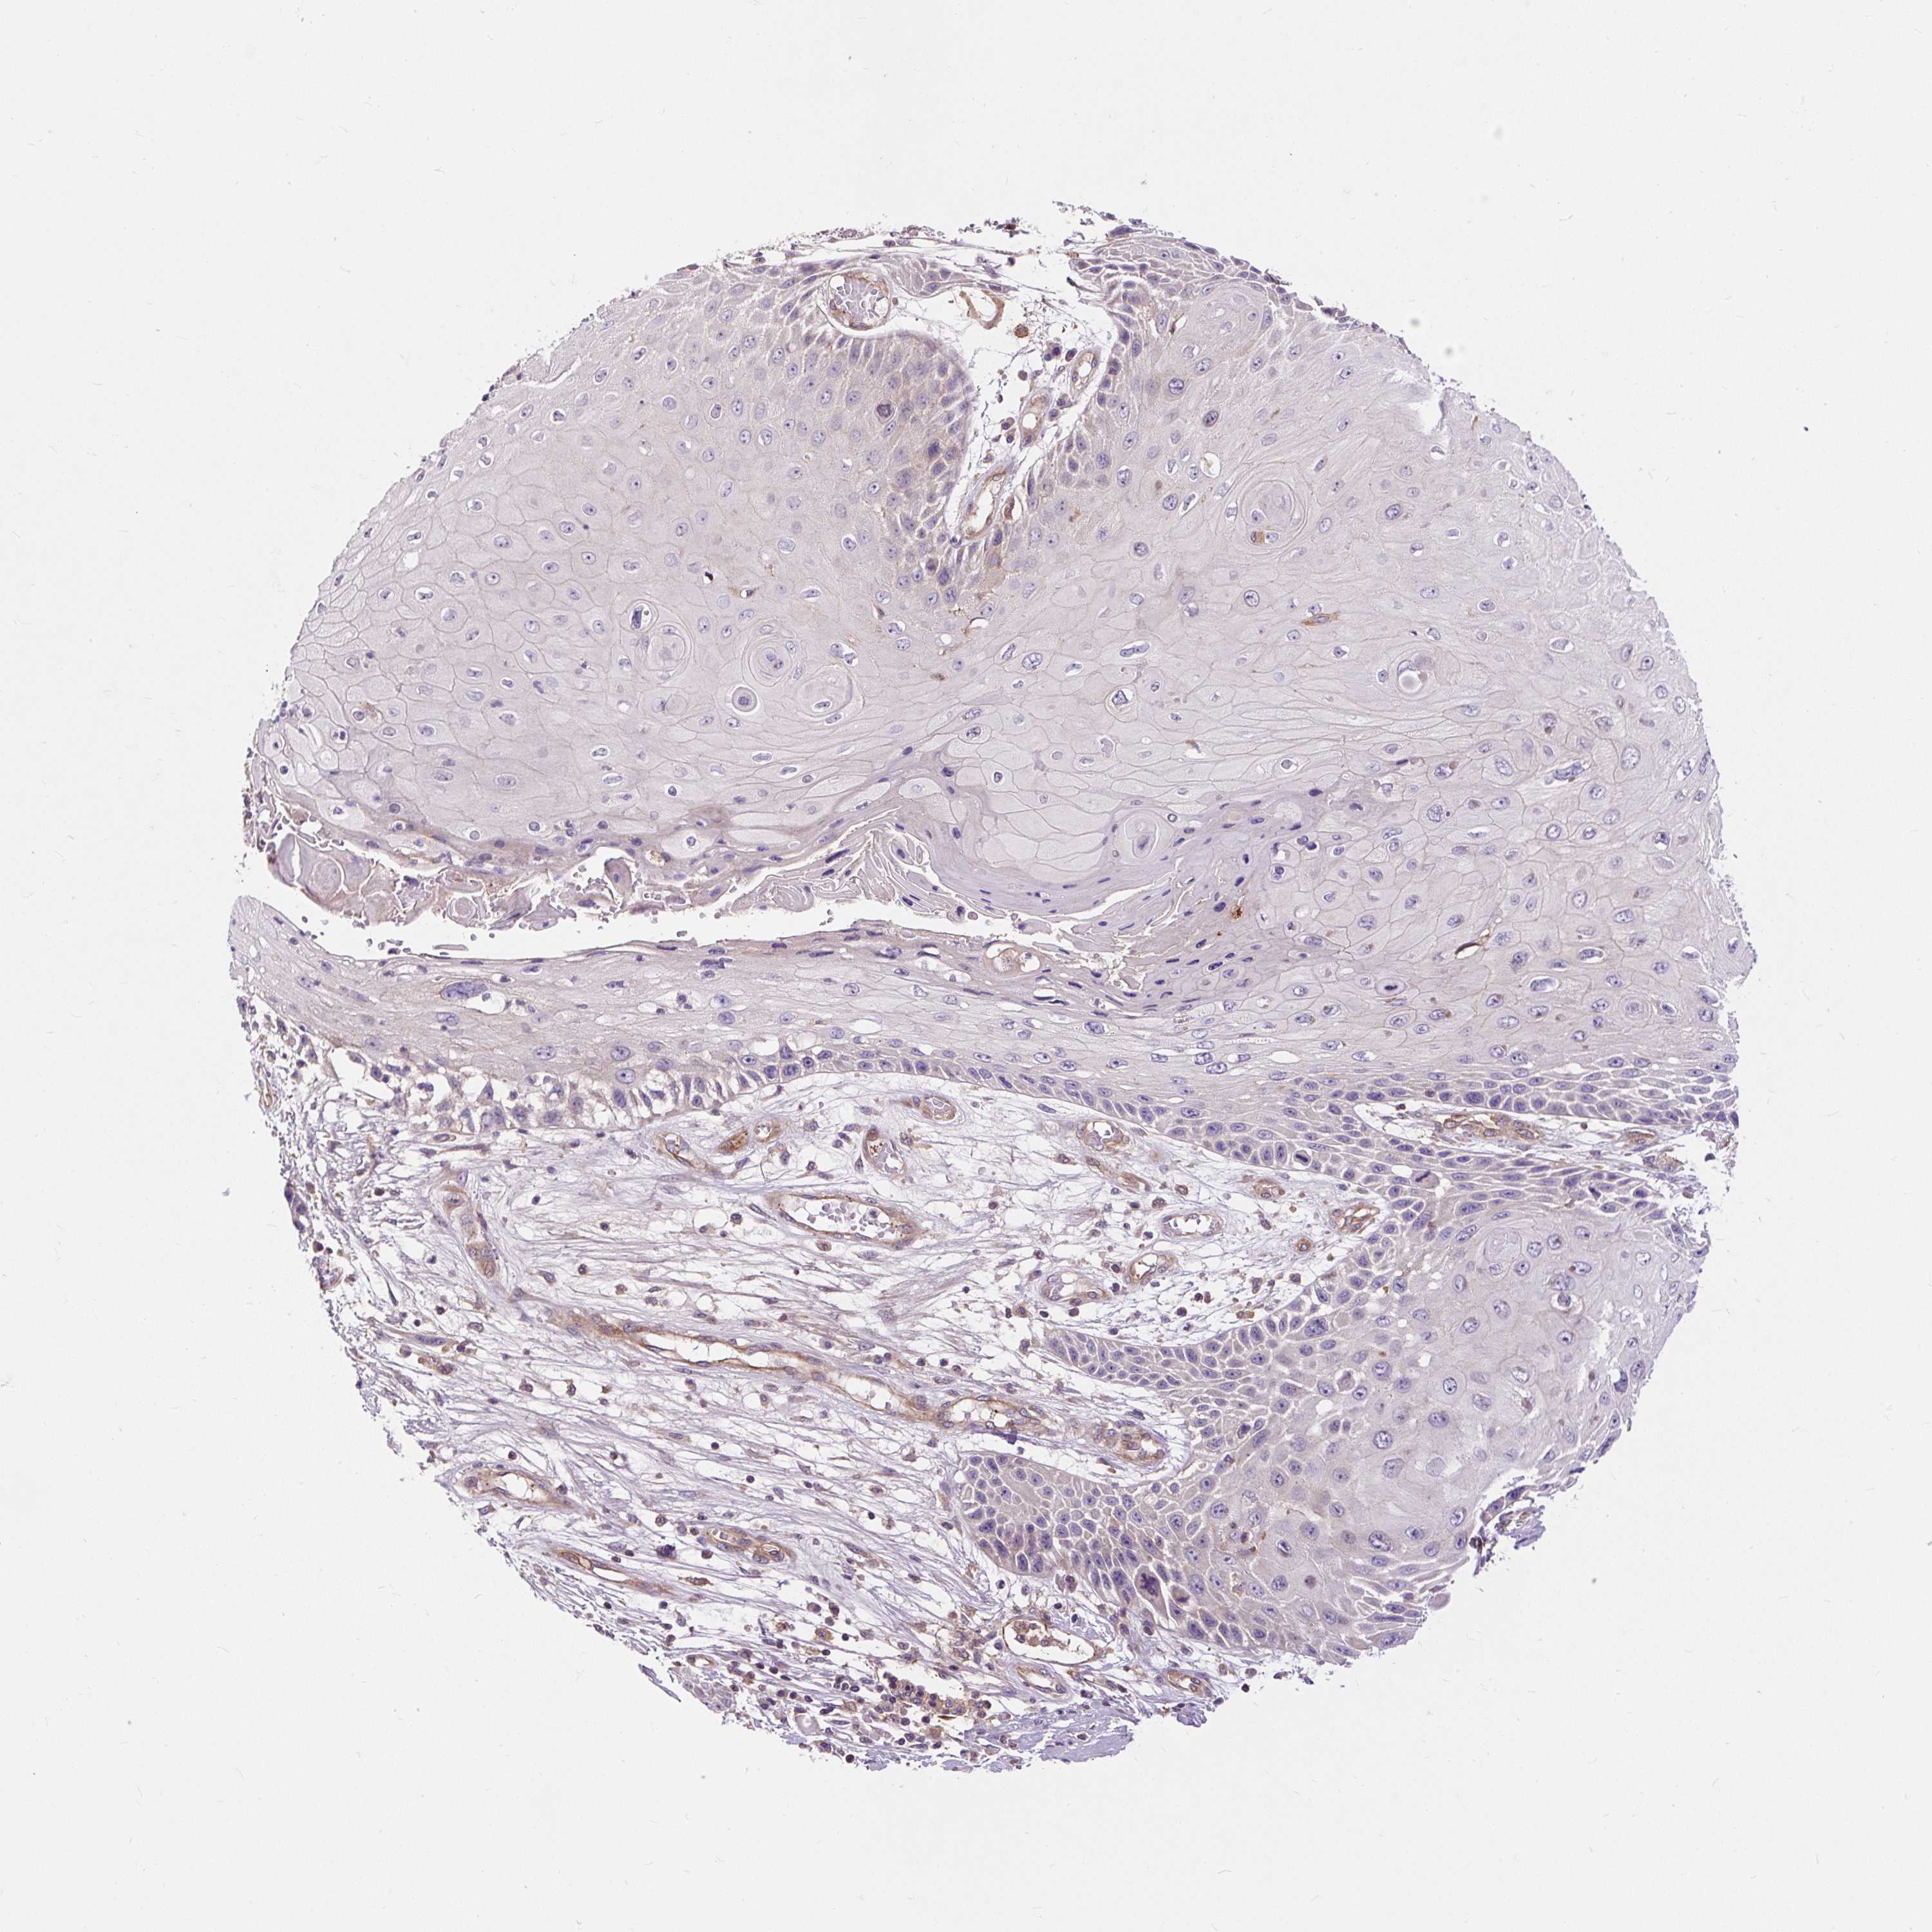

CANCER SKIN CANCER Show tissue menu

Basal cell and squamous cell cancer

SKIN CANCER - Protein expressioni

A mouse-over function shows sample information and annotation data. Click on an image to view it in a full screen mode. Samples can be filtered based on level of antibody staining by selecting one or several of the following categories: high, medium, low and not detected. The assay and annotation is described here.

Each image is clickable and will lead to virtual microscopy that enables deeper exploration of all samples and also displays staining intensity scores, fraction scores and subcellular localization as well as patient and tissue information for each sample.

Antibody HPA008755

Squamous cell carcinoma, NOS